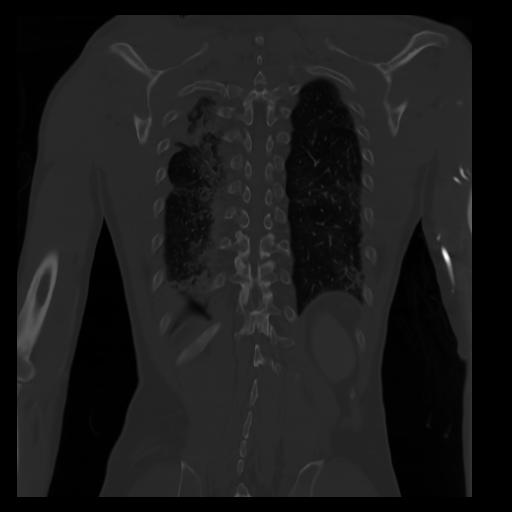

29 CUERPO,CE,Coronal,3.000,CUERPO,Coronal,